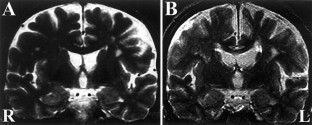

We report a Japanese autopsy case of progressive supranuclear palsy (PSP). The male patient was 74 years old at the time of death. At age 64, he developed non-fluent aphasia that progressed slowly over 8 years, eventually associated with behavioral abnormality, postural instability, and dysphagia at 2 years prior to his death. Magnetic resonance imaging of the brain at age 73 demonstrated marked atrophy of the frontal lobes, particularly on the left side. Neuropathological examination revealed the typical pathology of PSP: loss of neurons, gliosis, occurrence of neurofibrillary tangles, oligodendroglial coiled bodies, and tuft-shaped astrocytes in the frontal cortex, associated with argyrophilic threads in the underlying white matter, in the basal ganglia, including the thalamus, globus pallidus, and subthalamic nucleus, and in the brainstem nuclei, including the substantia nigra, pontine nucleus, and inferior olivary nucleus. No astrocytic plaques or ballooned neurons were observed. Protein analysis revealed accumulation of hyperphosphorylated tau of 68 and 64 kDa consisting of the four repeat tau isoforms. We conclude that the present case represented PSP with an 8-year history of primary progressive aphasia (PPA). Although focal cortical symptoms in PSP are rare or absent, we should keep in mind the possibility of atypical PSP in which cortical pathology is predominant, particularly in the frontal lobe, and could result in PPA.